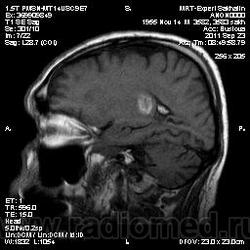

ID:53258

Онмк по геморрагичесому типу с образованием внутримозговой гематомы (подострая аза), прорывом в полость левого бокового и III -го желудочков.

Мужчина, вероятно, обычный гипертоник...

Это мой знакомый, но исследование проводилось не в мою смену.Сейчас находится в областном сосудистом центре.